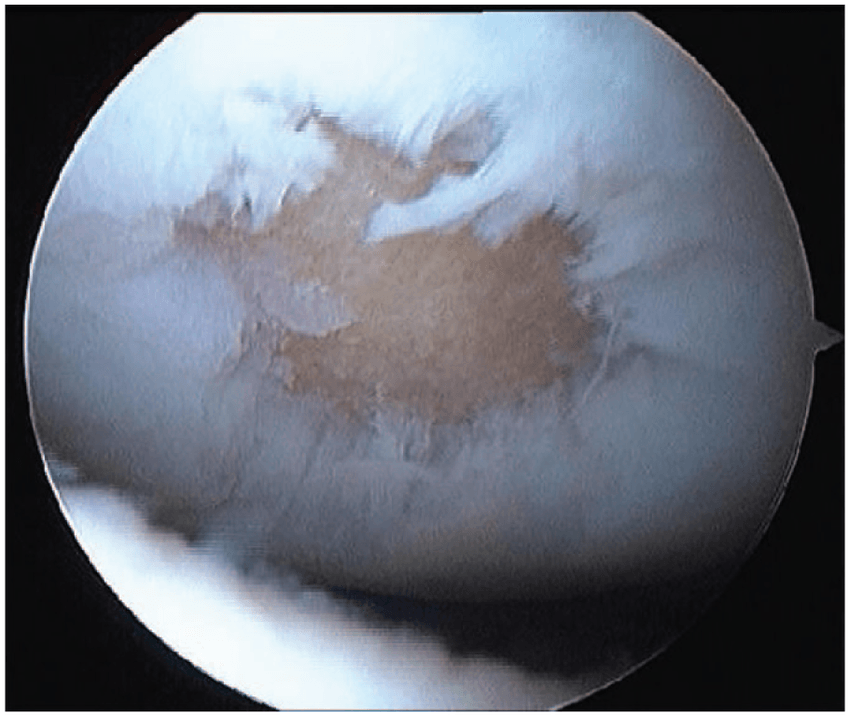

- Debridarea este o procedură artroscopică potrivită cartilajului distrus parțial. Prin această tehnică se netezesc suprafețele articulare prin curățarea cartilajului deteriorat. Se reduce astfel gradul de frecare între oase, pentru controlul durerii și a inflamației cauzate de edem (acumularea excesivă de lichid).

Procedurile artroscopice utilizate sunt tehnici chirurgicale minim invazive de diagnosticare și de reconstrucție (tratament), prin care se vizualizează în interiorul articulației, cu un instrument medical tubular, numit artroscop. Acesta funcționează ca o cameră video în miniatură, ce permite explorarea exactă a leziunilor din articulație și tratarea acestora cu instrumente specifice.